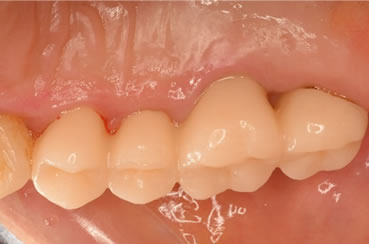

症例2

治療の特徴(患者Y様)

初診 2016年5月17日 / 経過 2018年7月2日

| 治療期間 | 2年2カ月 |

|---|---|

| 費用 | 保険内治療 |

| オペ費用 | 1ブロック約9,000円(3割負担) |

| 治療のデメリット | 歯内退縮が見られる。知覚過敏の症状が出ることがある。 |